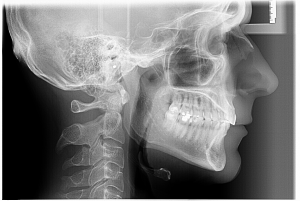

TELERADIOGRAFIE DE PROFIL – este un tip de radiografie craniană, realizată de la distanță, care oferă o imagine panoramică a feței, maxilarului, dinților și craniului dintr-o singură perspectivă laterală sau frontala. Această imagine permite evaluarea relațiilor dintre structurile osoase și dentare, a creșterii faciale și a fizionomiei, fiind un instrument esențial în ortodonție și alte tratamente dentare.

PRET: 150 Lei